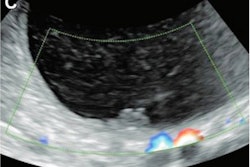

Paracentesis is performed for drainage of ascites, while thoracentesis is conducted for drainage of pleural effusions. A variety of specialties perform these minimally invasive procedures, which can be performed with or without ultrasound guidance.